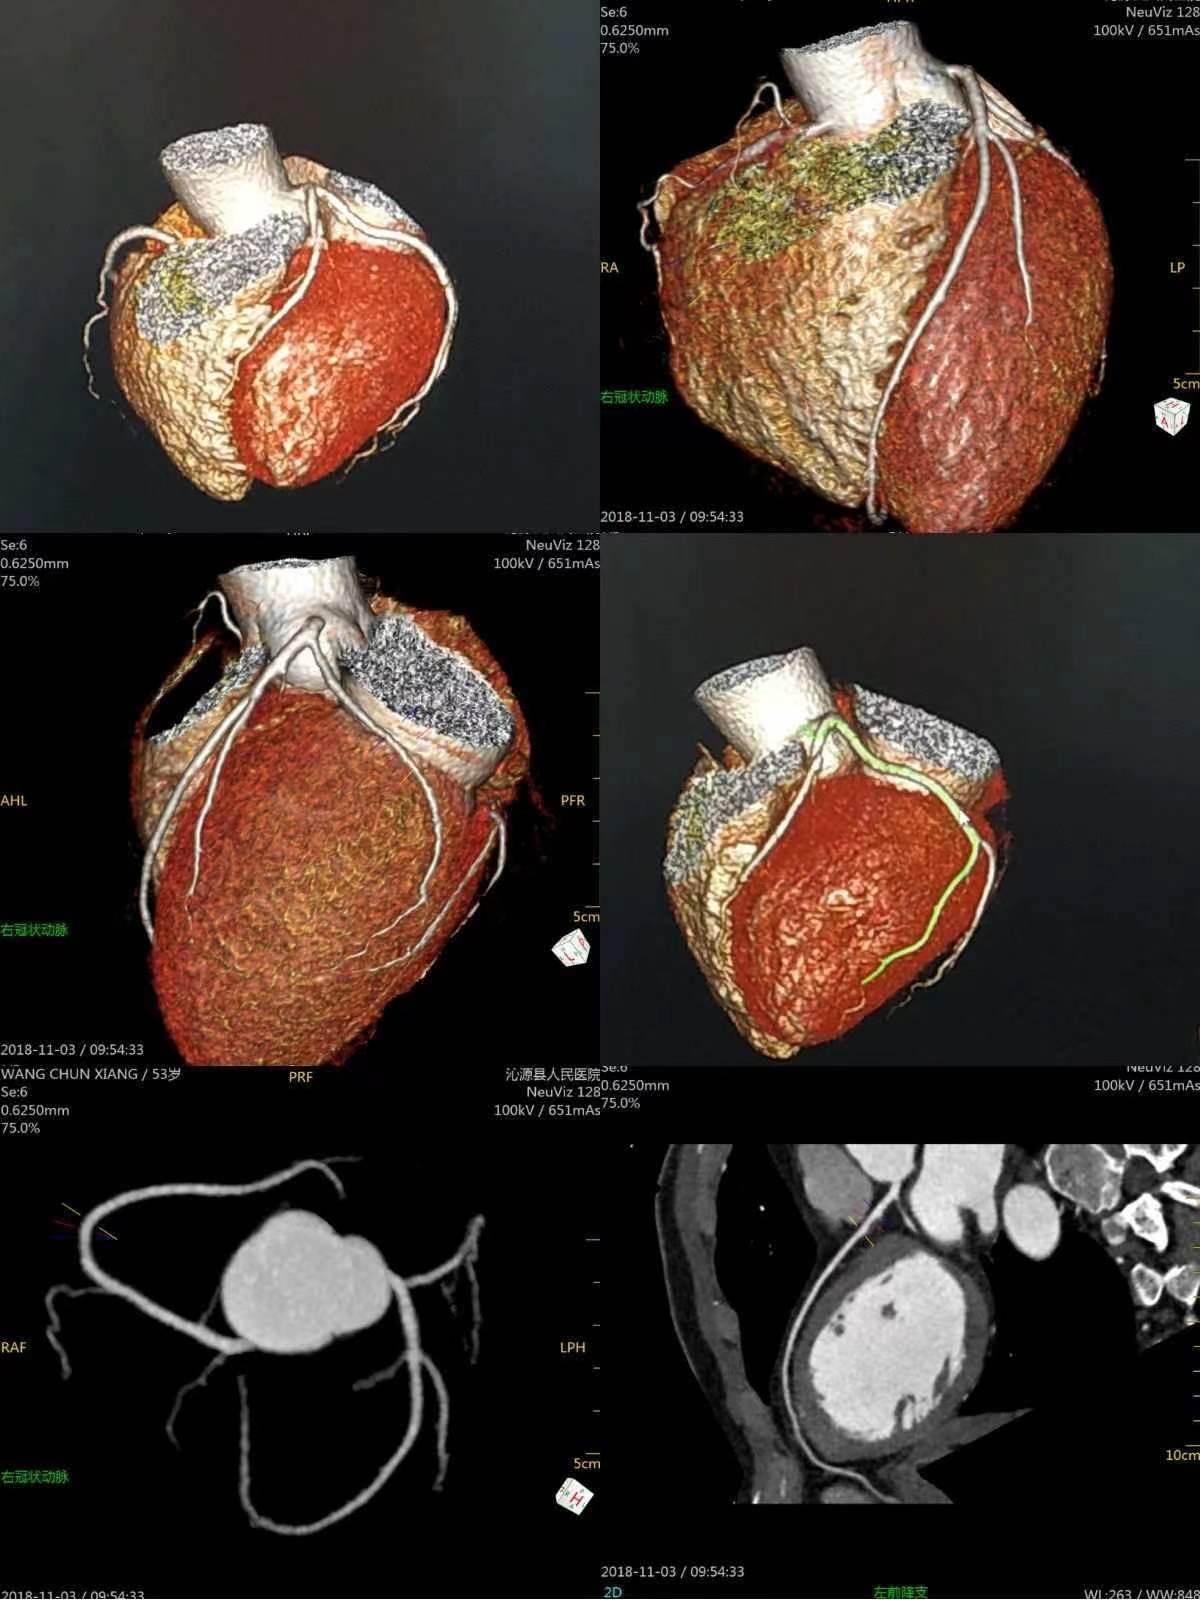

冠脉CTA检查是一种无创检查,通过经静脉注射造影剂后利用螺旋CT扫描再经计算机处理重建得出心脏冠状动脉成像。该检查主要用于冠心病的筛查,能够明确诊断患者有无冠状动脉狭窄,并评价斑块的性质与狭窄的程度。

图像后处理包括原始图像重建、判读图像和检查质量、三维重建和后处理等步骤,以确保检查结果的准确性和可靠性。